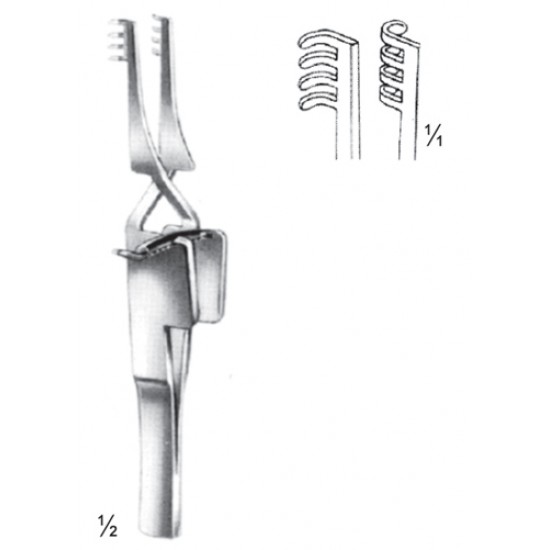

4U 16-4596-10

Self- Rataning Retractors, Holzheimer, 10 cm/3 7/8" Sharp

- Model: 4U 16-4596-10